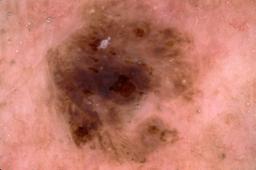

{

"age_approx": 85,

"anatom_site_general": "upper extremity",

"concomitant_biopsy": true,

"dermoscopic_type": "contact non-polarized",

"diagnosis_1": "Malignant",

"diagnosis_2": "Malignant melanocytic proliferations (Melanoma)",

"diagnosis_3": "Melanoma, NOS",

"diagnosis_confirm_type": "histopathology",

"image_type": "dermoscopic",

"lesion_id": "IL_4271814",

"melanocytic": true,

"patient_id": "IP_4497472",

"sex": "male"

}